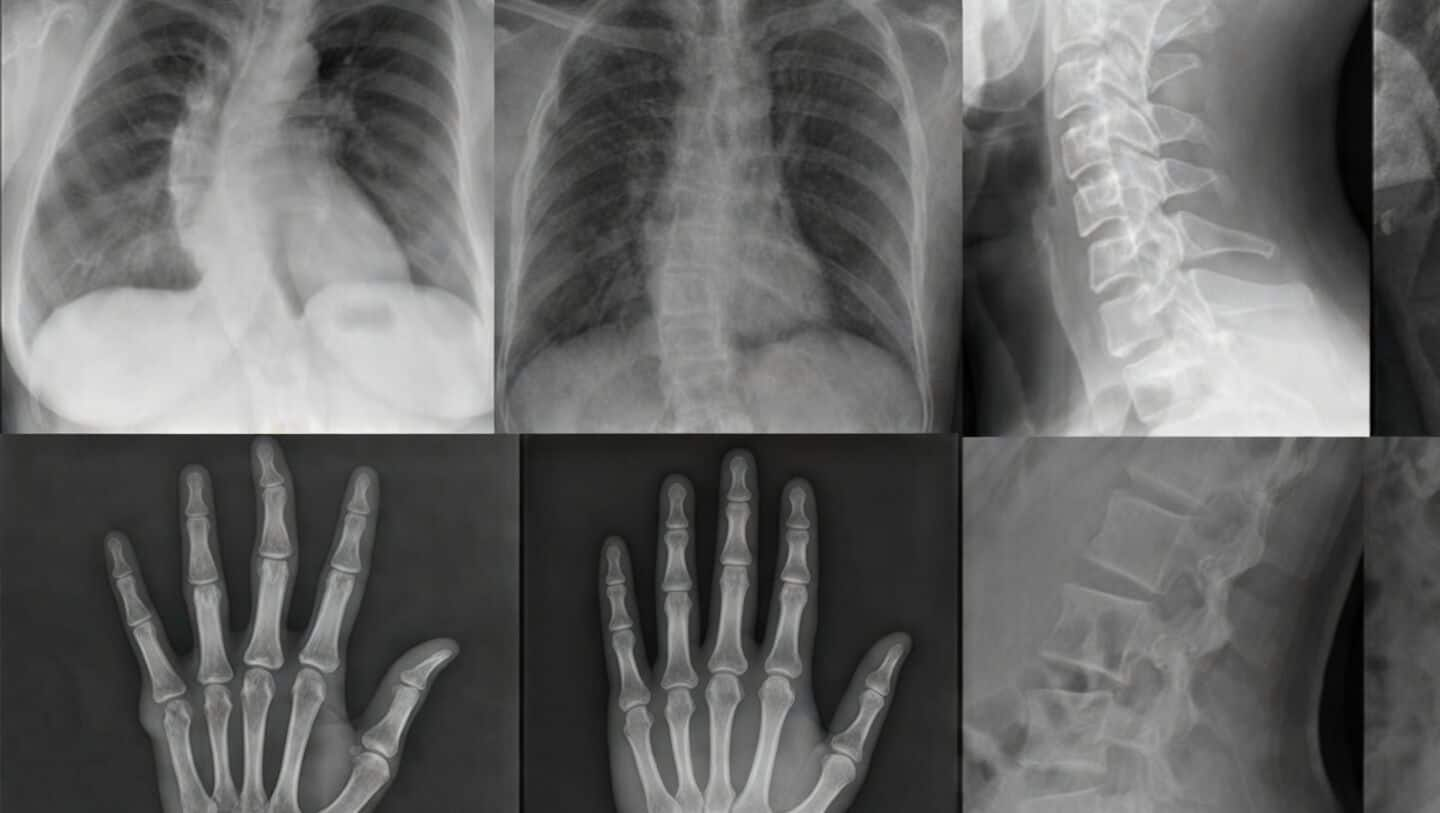

Mount Sinai study finds radiologists struggle to detect AI X-rays

Turns out, even experienced radiologists are having trouble telling real X-rays from ones created by AI.

A new study from Mount Sinai's Icahn School of Medicine had 17 radiologists from around the world try to spot fake medical images, and most found it surprisingly tough.

This raises some real concerns about deepfake X-rays sneaking into healthcare and making diagnoses riskier.